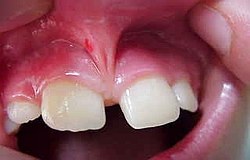

der Zahn will rauswachsen Durch den Druck schmerzt es sehr

Retinierte oder verlagerte Weisheitszähne haben keinen Platz im Kiefer. Beim aussichtslosen Versuch trotzdem herauszukommen, können Sie Nachbarzähne auflösen und schädigen oder das "das Gebiss verschieben. "Sie können auch Schmerzschübe auslösen . Deshalb sollten Sie besser entfernt werden. Wie bei jeder Operation muss vorher über mögliche Risiken wie Nervausfälle, Verletzung der Kieferhöhle und die Gefahr der Nachblutung aufgeklärt werden, selbst wenn die Wahrscheinlichkeit sehr gering erscheint. Die Risiken werden den voraussichtlichen Schäden durch den Verbleib des Weisheitszahnes gegenübergestellt. Erst nach Aufklärung und Einwilligung durch den Patienten wird der Eingriff durchgeführt. Bereits durchgebrochene Weisheitszähne sind oft schadhaft, da der Patient sie zum Putzen mit der Bürste fast nicht erreichen kann. Bevor sie als "Schmutzreservoir" auch den Nachbarzahn mit Karies anstecken sollte man sie besser ziehen. In diesem Fall verläuft die Extraktion einfacher mit weniger Risiken. Verhalten nach einer Operation. Manchmal ist der Zahn schon vorher inifziert oder entzündet sich nach der OP durch die Mundbakterien in diesem Fall muss die Naht wieder geöffnet werden und ein Medikamentenstreifen zum Ablass von Sekret und Eiter eingebracht werden.